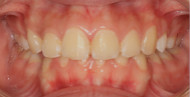

2019/07/1现在的我

开门见山,20岁,坐标广东,“以前牙不齐,两颗上门牙有点突,被人说是‘老鼠牙’,还有深覆颌(所谓的深覆合就是牙齿咬合状态时,上门牙盖住了下门牙,一般1/3是比较正常的,超过了1/3就被称为深覆合),导致了我每次拍照的时候从来都不笑,一定要笑,也是笑不露齿的那种。”真的很像假笑女孩~[○・`Д´・ ○].牙齿不齐,对口腔清洁也是非常遭罪,这个本人是深有体会啊

2019/08/30 戴了牙套笑的更自信了

今天来说说戴牙套感受吧,3-5天的时候还是有一点酸软,不能吃骨头、鸡爪这些硬的东西,习惯了之后觉得没什么了。现在就是吃什么都无所谓。身边的人也完全没有‘另眼相看’,可能是因为周围人也都是学医的,好几个朋友也在矫牙,大家都习以为常。矫了牙后,露出牙套也丝毫不在意,自己感觉比之前爱张嘴笑了,笑起来也自信大方,没有以前沉默不笑的样子了。期待牙齿渐渐排齐的样子(*^▽^*)